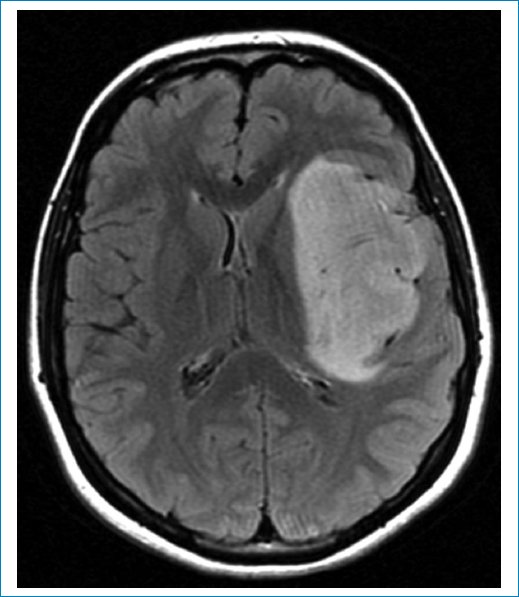

Las imágenes de resonancia magnética (RM) muestran una masa frontoinsular izquierda, hipointensa en la secuencia ponderada en T1 (Fig. 1), hiperintensa en T2 (Fig. 2) e hiperintensa en FLAIR (Fig. 3), pero con centro de menor intensidad. Este hallazgo, llamado “signo de la discrepancia”, es propio de las neoplasias gliales con IDH (isocitrate dehidrogenase) mutado y sin codeleción en 1p/19q1,2, y se observa en los astrocitomas. La codeleción 1p/19q es propia de los oligodendrogliomas3,4. La volumetría indica un volumen de 84 cm3 (Fig. 4).

Figura 2. Secuencia ponderada en T2. Masa hiperintensa.

Figura 3. Secuencia FLAIR. Hiperintensidad mayor en la periferia (“signo de la discrepancia”), típica de los gliomas, IDHm sin codeleción 1p/19q.